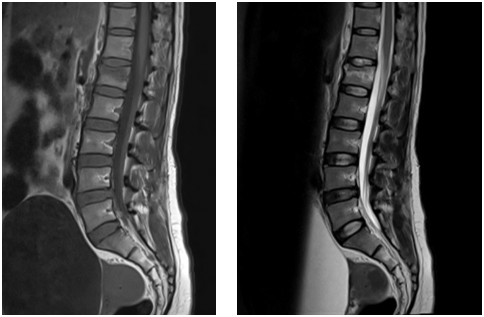

Chiều18/11, bệnh nhân đã được các bác sĩ  tại đơn nguyên Tim mạch can thiệp (DSA) và Khoa Ngoại CTCH tiến hành thủ thuật đổ xi măng cột sống số hóa xóa nền (DSA). Ngay ngày hôm sau, bệnh nhân đã đứng thẳng, đi lại bình thường.

Hình ảnh bơm xi măng vào thân đốt sống L1